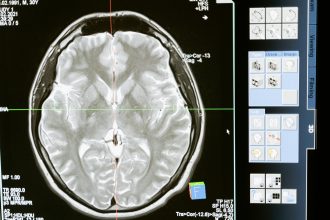

Protected by the skull and cushioned by fluid, the brain weighs about three pounds, yet it consumes nearly 20 percent of the body’s oxygen and energy. It is divided into major regions, each performing specialized but interconnected roles.

The cerebrum is the largest and most recognizable part of the brain. It’s divided into left and right hemispheres, connected by a thick band of nerve fibers called the corpus callosum.

Each hemisphere controls the opposite side of the body — the left hemisphere governs the right side, and vice versa. Within the cerebrum are four lobes, each responsible for distinct functions: